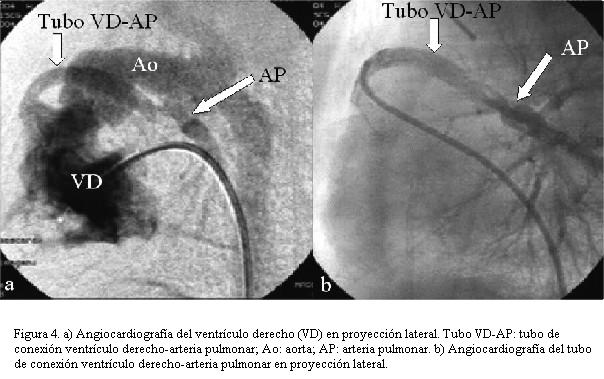

Los principios quirúrgicos consisten pues en obtener una comunicación permanente, no obstructiva, entre el ventrículo único derecho y la aorta, limitar el flujo sistémico pulmonar sin distorsionar su arquitectura y aliviar la obstrucción venosa pulmonar con una amplia atrioseptostomía (figura 4) (3).

A los dos meses el estudio hemodinámico comprueba estenosis proximal y distal del tubo VD-AP realizándose angioplastia con catéter balón.

Se reestudia al mes en hemodinamia comprobándose estenosis proximal del tubo protésico por lo que se efectúa angioplastia con balón.